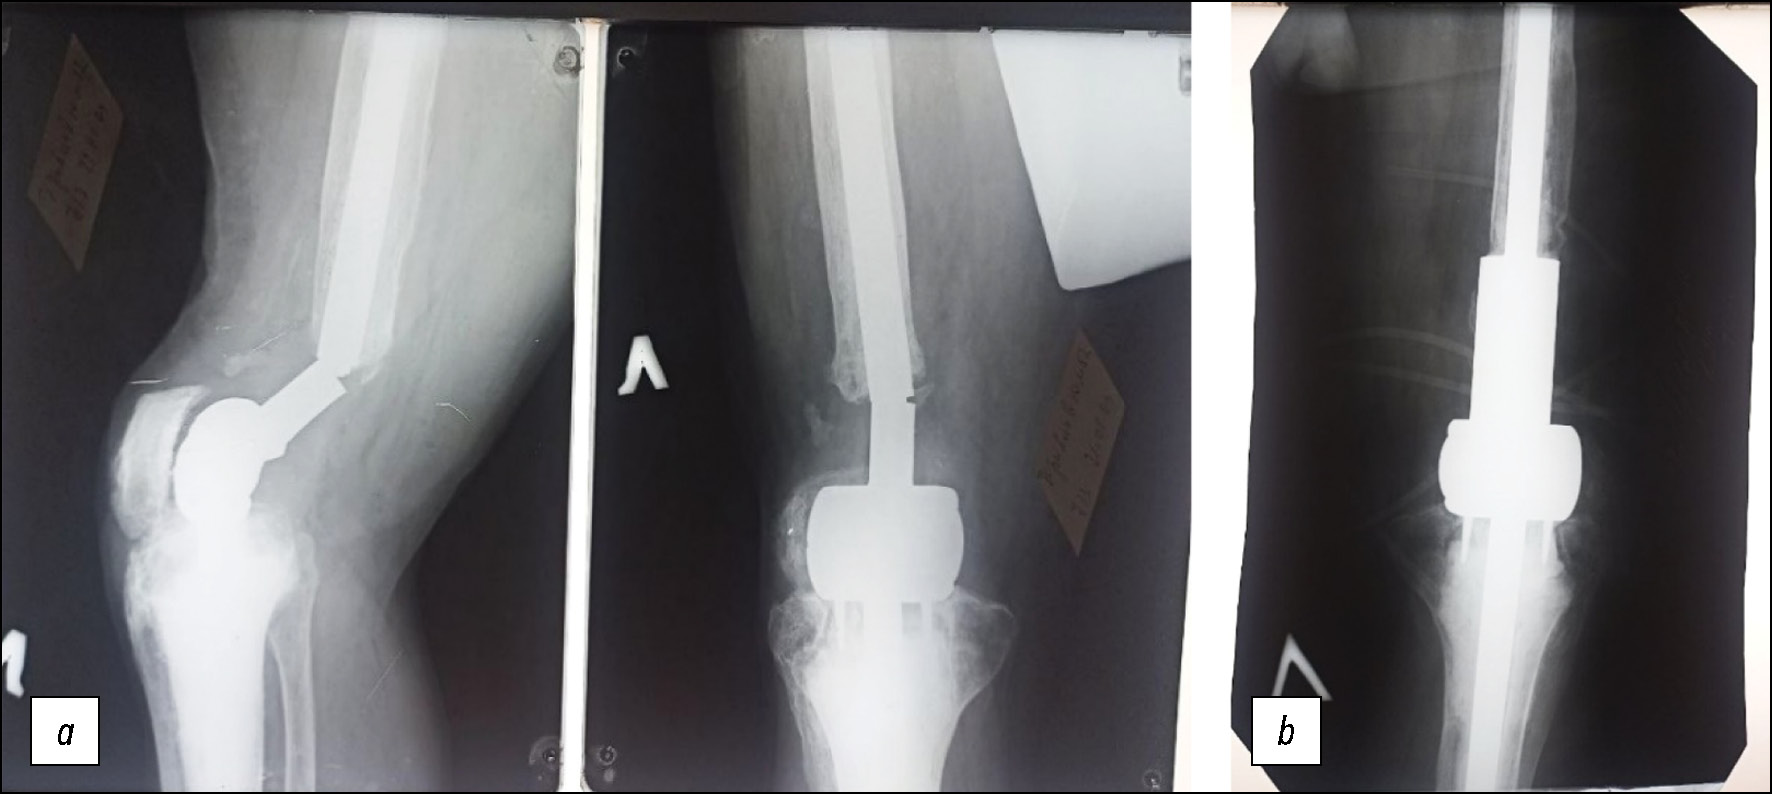

В 2017 году вновь упал, резко согнув ногу в коленном суставе. Отметил сильную боль и выраженное ограничение движений в суставе. На рентгенограммах выявлена миграция большеберцовой части узла подвижности эндопротеза из цементной мантии, окружающей ножку (рис. 6а). Больному был изготовлен большеберцовый компонент эндопротеза с дополнительной втулкой, усиливающей место соединения узла подвижности с ножкой.

Рис. 6. Рентгенограммы: a — до, b — после замены большеберцового компонента эндопротеза коленного сустава Сиваша.

Fig. 6. Radiographs: a — before, b — after replacement of the tibial component of the Sivash knee joint endoprosthesis.

В июле 2017 г. выполнена замена повреждённого большеберцового компонента эндопротеза Сиваша на усиленную конструкцию с её цементной фиксацией в проксимальном отделе большеберцовой кости (рис. 6b).

Пять лет больной был полностью удовлетворён результатом операции, но осенью 2022 года при езде на велосипеде был сбит скутером, после чего появились боли в проксимальном отделе левой голени при нагрузке и движениях. Пациент был вынужден передвигаться с помощью костылей, ограничивая нагрузку на конечность. На рентгенограммах выявлена резорбция кости вокруг цементной мантии, фиксирующей ножку эндопротеза в проксимальном отделе большеберцовой кости. В связи с нарушением фиксации в кости этот компонент необходимо было заменить (рис. 7а).

Рис. 7. Рентгенограммы: a — до, b — после имплантации удлинённой ножки эндопротеза коленного сустава.

Fig. 7. Radiographs: a — before, b — after implantation of the elongated leg of the knee joint endoprosthesis.

Был изготовлен большеберцовый компонент эндопротеза Сиваша с удлинённой ножкой и в июне 2023 года осуществлены удаление нестабильного большеберцового компонента эндопротеза вместе с цементной мантией и установка изготовленного компонента с удлинённой ножкой (рис. 7b). Компонент фиксирован в кости с помощью костного цемента и дистальных блокирующих винтов. Через две недели после операции пациент был выписан на амбулаторное наблюдение по месту жительства с рекомендацией дозированной нагрузки на конечность сроком до трёх месяцев. Через три месяца после операции ходит с помощью трости. Боли в суставе не беспокоят. Амплитуда движений в суставе от 180 до 90 градусов. Устроился на работу сторожем на одном из предприятий г. Геленджика. Несмотря на весь трагизм истории нашего пациента и переживаний врачей о планировании и исходе его многочисленных операций, сам пациент результатом лечения во всех случаях был доволен.